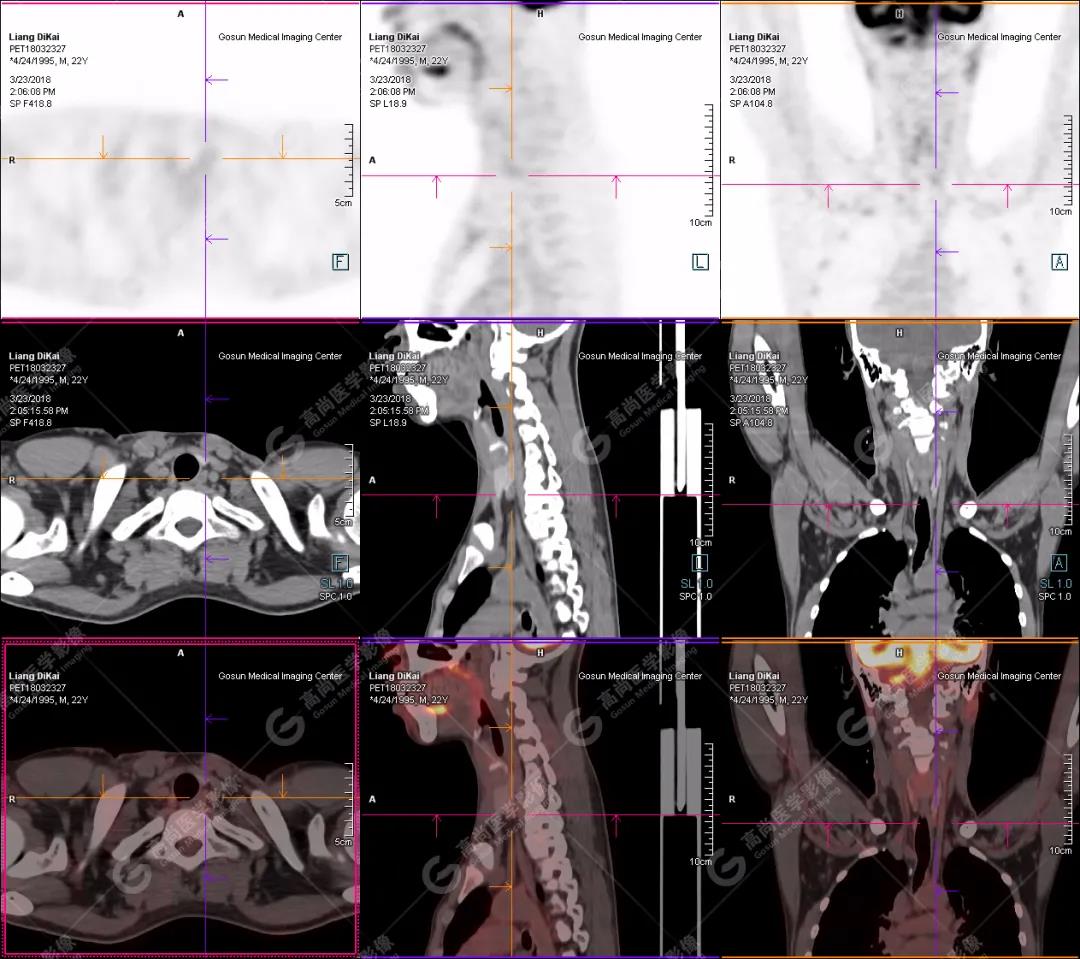

1.右肘關(guān)節(jié)周圍、骶尾部皮下、雙側(cè)臀部、盆腔左側(cè)壁及左側(cè)大腿根部肌肉、肌間隙多發(fā)結(jié)節(jié)狀、片塊狀及不規(guī)則巨塊狀高密度鈣化灶,伴代謝不均勻輕度增高,考慮為鈣質(zhì)沉著癥;

2.甲狀腺雙葉后方多發(fā)(右2個,左1個)小結(jié)節(jié)狀軟組織影,部分代謝輕度增高,多考慮為甲狀旁腺腺瘤。